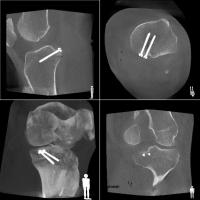

一例として、金属のボルトを骨内に挿入する際に、位置や角度、深さを様々な方向から観察できるほか、装置を回転させて撮影することで、CT画像のような自由な断面像を得ることも可能です。